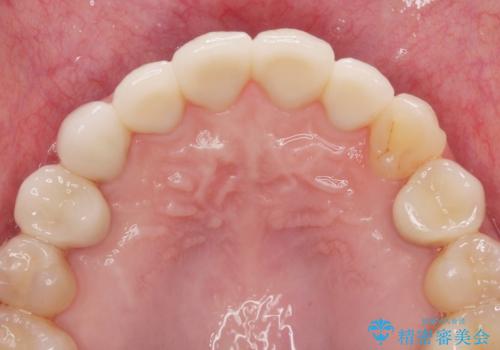

多発した前歯の重度虫歯治療

まず虫歯を拡大鏡、マイクロスコープ下で丁寧に取り除き歯肉縁下の虫歯を歯周外科により解決したのち、ジルコニアクラウン製作を行っていきます。

丁寧な虫歯の除去・歯周組織の整備、適合の良い精密なセラミッククラウンの製作といった丁寧な治療の積み重ねが良好な治療結果を得ることにつながります。